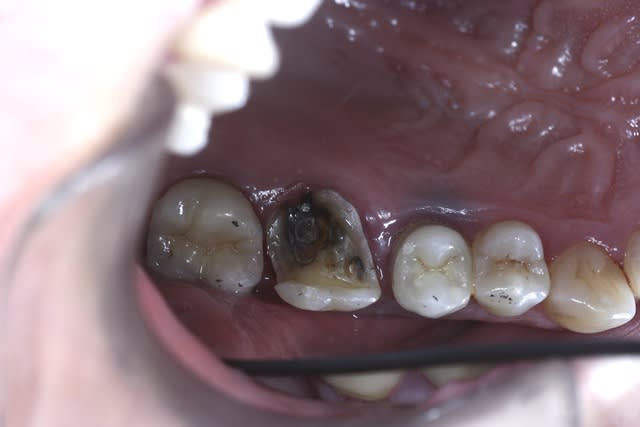

Je me suis lancé, on va voir ce que ça va donner la semaine prochaine. On mutile un peu moins c'est vrai, surtout qu'avec une prépa de dépouille pour une couronne on dézingue de fait beaucoup plus dans la partie occlusale.

J'ai tout recouvert en occlusal avec congé large.

Mis-à-part que les photos sont celles de ma cam (Chinese inside) qu'est-ce que j'aurais du faire ou ne pas faire ?

Assez nase l'onlay Emax en couleur (B2.5 demandée, les deux teintes à côté B2 et B3), en sculpture mais là je suis responsable, j'aurais dû ménager plus de place.

J'ai etché silané mais aurais-je dû ? J'ai pris du G-Cem, j'ignore si c'est aussi efficace qu'en collage classique.

J'ai posé une digue sur la seule dent, erreur car avec l'épaisseur de la feuille, ça passe plus en proximal, donc j'ai maintenu l'élément encollé au pouce, retiré tout le tintouin en vitesse et retrouvé un torrent salivaire menaçant.

À la réflexion à froid j'aurais dû donner deux coups de ciseau/scalpel sur la digue en proximal, ç'aurait été mieux en dépannage.

Je ne sais pas encore quelle compo auto prendre pour les collages, la teinte a probablement été altérée par le G-Cem. Il y a le classique Variolink pratique avec ses seringues à produit hydrosoluble pour essai esthétique mais est-ce le meilleur produit ?

Il n'y aurait pas eu une languette profonde en distal j'aurais pris un compo photo et insolé au travers de l'onlay.